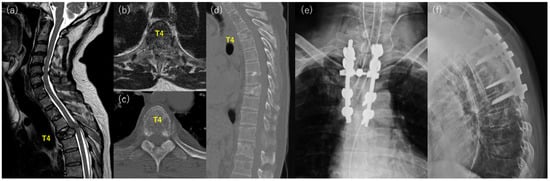

Case 2: A 60-year-old man with back pain was referred to our hospital for further examination and treatment (Figure 2). Imaging studies showed multiple metastases of the spine, and vertebral collapse and spinal cord compression were found at T4 (Figure 2a–d). He had no history of malignancy, but a biopsy of the spinal lesion and the imaging study revealed lung adenocarcinoma. He could walk without neurological deficits at presentation, and radiation therapy was initiated. However, motor weakness progressed during this period, and he underwent posterior decompression with stabilization from T2 to T6 (Figure 2e,f). The motor weakness improved immediately after surgery. However, respiratory status progressively worsened due to exacerbation of primary cancer, and the patient died 10 days after the surgery.

Figure 2. Representative case of the poor outcome group with T4 spinal metastasis from lung adenocarcinoma. (a) sagittal image and (b) axial image of preoperative T2 weighted MRI, (c) axial image and (d) sagittal image of preoperative CT, (e) anterior-posterior, and (f) lateral postoperative X-ray.